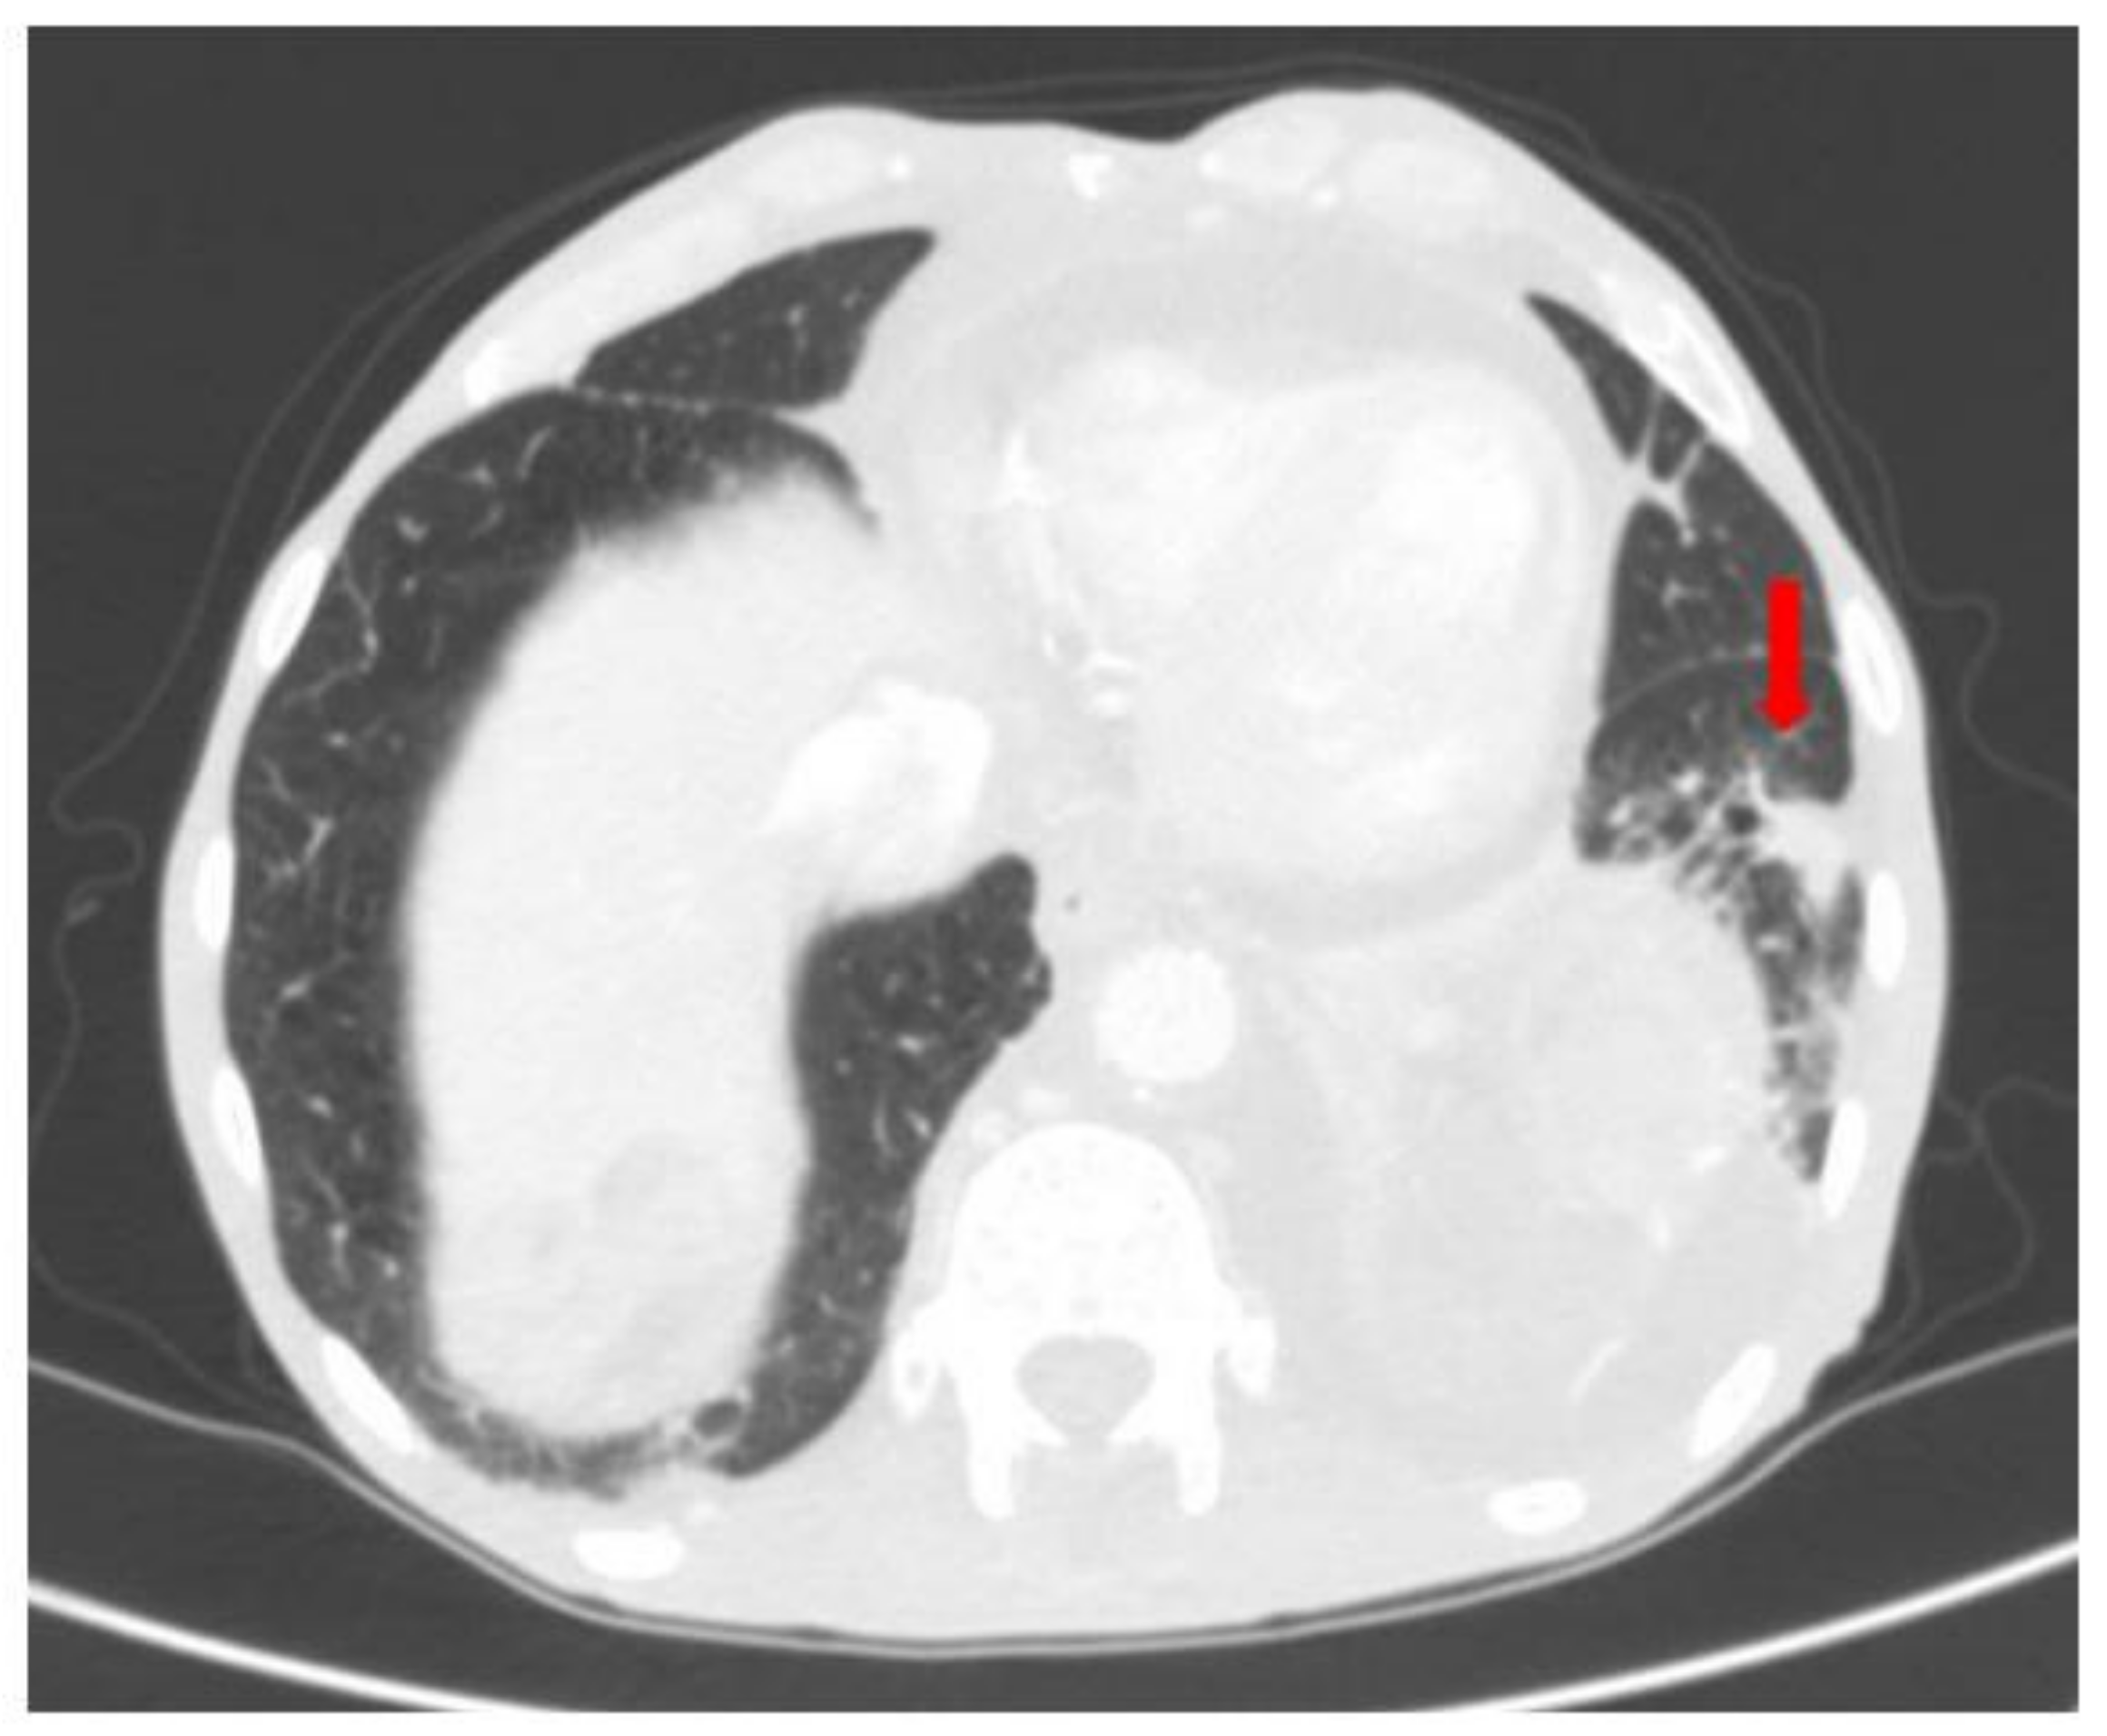

2. Case Report